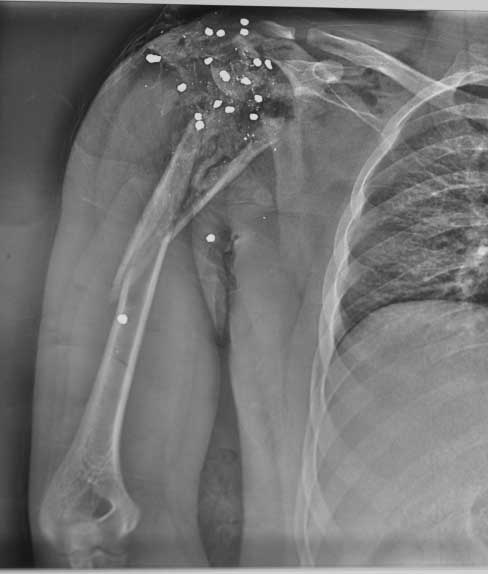

Молодой человек 25 лет поступил с огнестрельным ранением области плечевого сустава.

травма 12.05.12 - огестрельное ранение правого плечевого сустава, открытый

многооскольчатый перелом проксимального отдела плеча с переходом на диафиз. стреляли

практически вупор. Входное отверстие округлое диам 3 см по передней поверхности

дельтовидной области, выходных отверстий множество диам до 0,5 см больше по задне верхней

поверхности дельтовидной области. при поступлении - ПХО при ревизии - удален пластиковый

пыж, повреждена вся дельтовидная мышца частично повреждены надостная подостная мышцы,

капсула сустава разорвана в клочья,сухожилия ротаторной манжеты также разорваны в кашу,

головка плеча - ее не было - просто костная каша в ране, кроме того выявлен перелом акромиона.

гленоид практически не пострадал. Рана промыта нежизнеспособные ткани иссечены, костная

крошка удалена. швы на рану, перелом стабилизирорван стержневым аппаратом. На сегодняшний

день - рана без воспаления, заживление первичное. Движения в кисти, локтевом суставе в

полном объеме. Вопрос к уважаемому сообществу - что делать? С уважением Леонид Пак